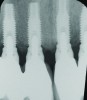

Fig 16 and Fig 17. Clinical photographs demonstrating bone loss and recession 20 years after prosthesis insertion. Initially the gingival margin covered the implant collars and threads. Fig 16: maxillary right; implants were placed at site Nos. 3 through 6. Fig 17: maxillary left; implants were placed at site Nos. 10 through 13.

This assessment presumed patients were healthy. However, there are situations that can contribute to bone loss and individuals may experience a greater amount of osseous resorption than reported in this evaluation: systemic conditions (eg, diabetes, osteoporosis); smoking; medications (eg, bisphosphonates)90,91; subgingival cement retention92 and peri-implantitis; and in some patients, time appears to be a factor (Figure 16 and Figure 17).93 Furthermore, there are patients that lose more bone around implants than expected in the absence of recognized risk factors. It could be speculated that occlusal forces contributed to this, but that is also controversial.94